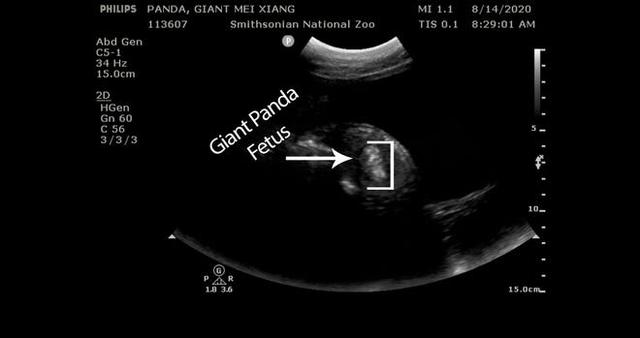

华盛顿国家动物园上周五就公布了美香可能怀孕的消息 , 本周一 , 动物园又在官方社交网站上发布了一段美香的超声波检测视频 , 视频中可以看到熊猫胚胎 。 动物园首席兽医表示 , 视频显示出了胚胎的心跳和骨骼结构 。